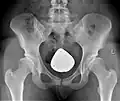

Diagnostik

Sowohl zur genauen Beurteilung der Hüftdysplasie und ihres Schweregrades, als auch zur Planung der Operation werden konventionelle Röntgenbilder des Beckens, sogenannte Beckenübersichtsaufnahmen, angefertigt.

Computertomographien (CT) oder Magnetresonanztomographien (MRT) sind nur in Ausnahmefällen notwendig, um z. B. den Grad der Gelenkschädigung besser beurteilen zu können. Computerverfahren zur dreidimensionalen Darstellung von Organen haben sich im Bereich des Beckens nicht etabliert. Jedoch kommt das 3D-CT des Beckens bei CT-gestützten Navigationsverfahren (siehe unten) zum Einsatz.[7]